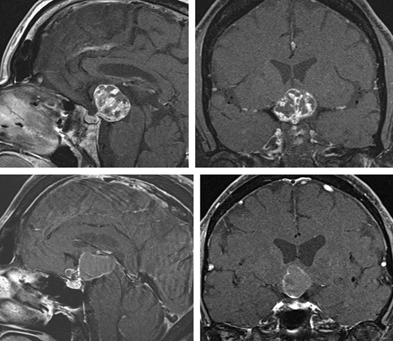

MRI of the pituitary 05.02 (Figure 4).

• The study shows the already identified lesion extending from the pituitary fossa superiorly compressing the pituitary gland anteriorly, inferiorly, and posteriorly

• 47cm X 1.67 cm in size

• The optic chiasm is displaced superiorly.

• The lesion abuts the right Internal carotid artery.

• The lesion is of smooth outline hyper intense in signal with a small soft tissue component isointense in all sequences…

Conclusion

The imaging findings are those of Craniopharyngioma (Figure 4).

Figure 4